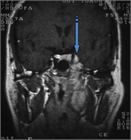

1. 原発巣の進展範囲診断にはCTに加えMRIが推奨される(推奨度2 SJG)